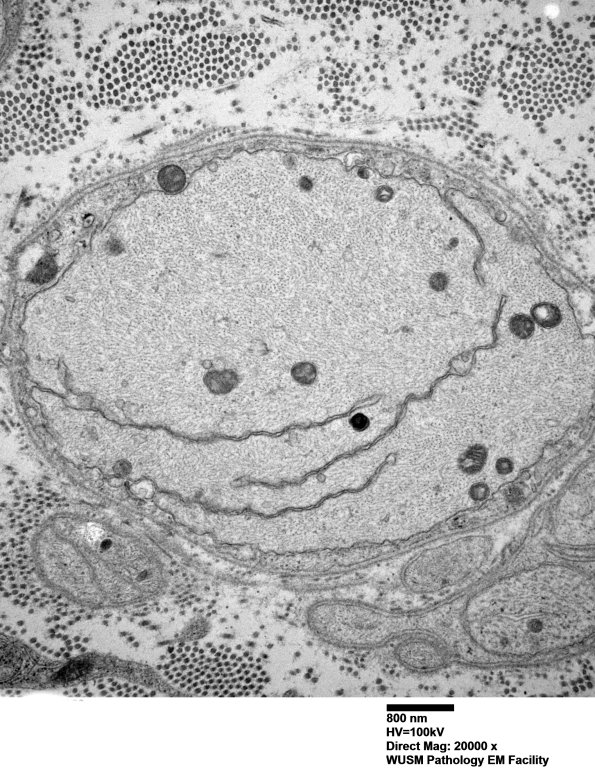

These processes do not seem to represent a simple artifact. Note filamentous structures. (electron micrograph)